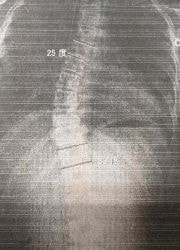

レントゲンのビフォーアフター)

写真1(施術前) 写真2(5か月後)

○コブ角上27度⇒25度(2度改善)、下40度⇒33度(7度改善)

※コブ角は専門医の診断